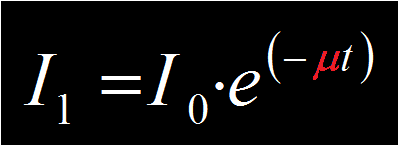

The X-rays propagate through the sample where some of the X-ray photons are absorbed and others are transmitted to the detector. The general form of X-ray attenuation is:

Where:

I0 = X-ray intensity before reaching object

I1 = X-ray intensity after passing through object

e = the exponential coefficient (2.7182818……….)

μ = the x-ray attenuation coefficient

t = the thickness of the absorbing material, in chosen distance units e.g. mm